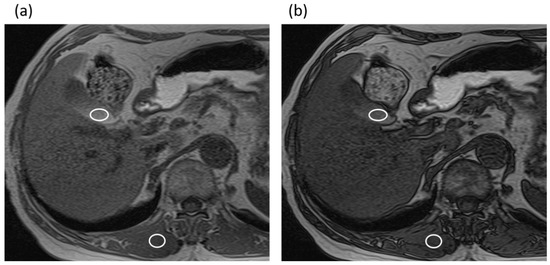

The three radiologists measured the maximal diameter of the common bile duct perpendicularly to the long axis of the duct on MRCP images without the IR pulse by using an electronic caliper. The averaged common duct diameter of the two radiologists’ measurements was used for the data analysis. In addition, the three radiologists also measured the signal intensities (SIs) of the gallbladder (SIgallbladder) and paraspinal muscle (SImuscle) on the T1-weighted gradient-echo in-phase and opposed-phase images using operator-defined regions of interest (ROIs), in consensus. The signal intensity of gallbladder is often heterogeneous, forming gradational layering. Therefore, an effort was made to draw the ROI circles as large as possible in a high-signal area of the gallbladder on the in-phase images while avoiding the gallstones and artifacts, and the ROI was then copied and pasted on the opposed-phase images (Figure 2). The SI ratio (SIR) was then calculated from the SIgallbladder and the SImuscle as SIgallbladder/SImuscle in each image. In addition, the signal reduction ratio (SRR) was calculated as follows: SRR = [(SIR in-phase) − (SIR opposed-phase)]/(SIR in-phase).

Figure 2.

An 82-year-old man with intraductal papillary mucinous neoplasm in the non-gallstone group. (a) T1-weighted gradient-echo in-phase image. The gallbladder-to-muscle SIR was 2.12. (b) T1-weighted gradient-echo opposed-phase image. The gallbladder-to-muscle SIR was 1.72. The SRR of the gallbladder was 0.19.

In analyzing the SIR of the gallbladder, the SIR on T1-weighted gradient-echo in-phase imaging was significantly lower in the gallstone group than in the non-gallstone group (1.2 (range, 0.77–1.51) vs. 1.62 (range, 1.2–2.12)), while there were no significant differences in the SIR for T1-weighted gradient-echo opposed-phase imaging between the groups (p = 0.210). In addition, the SRR of the gallbladder was significantly lower in the gallstone group than in the non-gallstone group (0.11 (range, −0.029–0.36) vs. 0.35 (range, 0.23–0.42)).